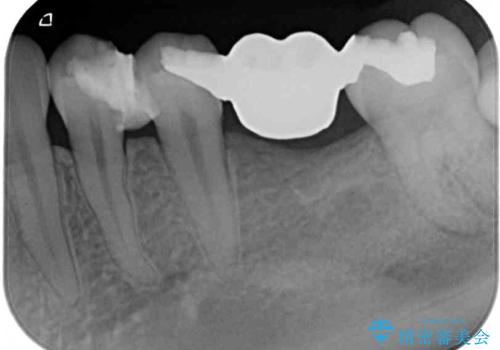

- ブリッジの歯のないところにインプラントを入れて、銀歯を白くやり替えたいと来院された患者様です。

歯の欠損している箇所にはインプラント治療をし、銀歯と仮詰めの部分はセラミックインレーにて補綴することとしました。

すべての治療の前に親知らずの抜歯も行っています。